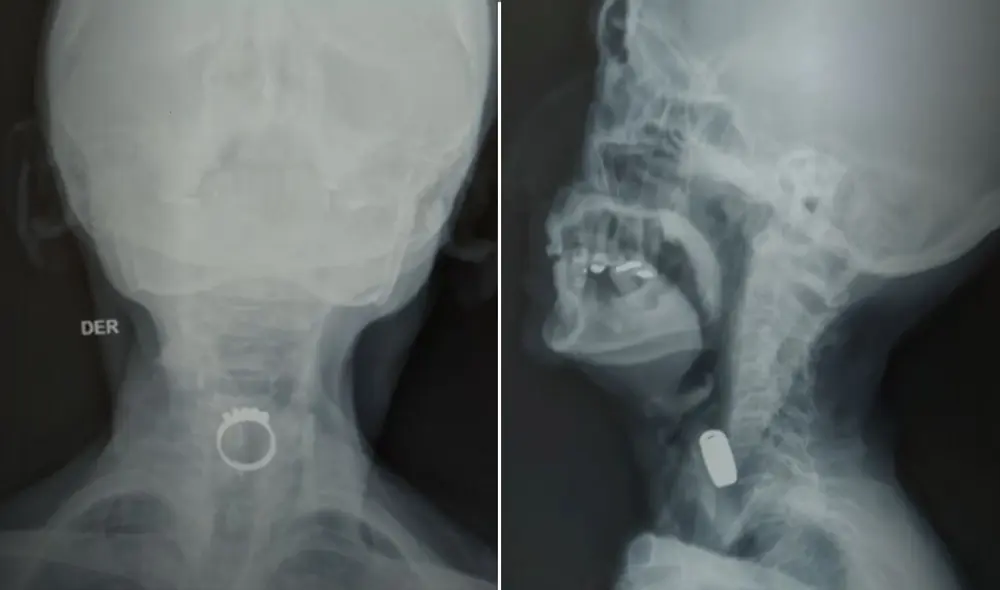

Una mujer de 85 años fue sometida a una endoscopia tras tragar un anillo mientras dormía. La situación se volvió crítica al notar problemas para respirar, lo que llevó a su familia a actuar de inmediato.

Una mujer de 85 años, identificada como Victoria Consuelo la Rosa Díaz, fue sometida a una cirugía de emergencia tras ingerir un anillo mientras dormía. La situación se tornó crítica cuando la paciente comenzó a manifestar dificultades para respirar, lo que llevó a su familia a actuar rápidamente.

Victoria, quien según su familia padece demencia por cuerpos de Lewy, una enfermedad de deterioro neurodegenerativo que afecta la memoria, el pensamiento y el comportamiento, soñó que comía un caramelo y, al despertar, se dio cuenta de que había tragado un anillo. Su hija, Cecilia Díaz, relató que la mujer comenzó a toser y a expresar que no podía respirar, lo que generó una gran preocupación en su familia. La rápida movilización del equipo médico del Hospital Arzobispo Loayza fue crucial para atender esta emergencia.

El incidente ocurrió en la madrugada de este martes, cuando Victoria fue llevada al hospital tras presentar síntomas de asfixia. Su hija explicó que, al despertar, la mujer comenzó a toser de manera persistente y a manifestar que sentía un objeto alojado en su esófago. A pesar de que podía respirar, la sensación de incomodidad era alarmante. La familia decidió buscar atención médica inmediata, lo que resultó ser una decisión acertada.

Al llegar al hospital, se realizaron los exámenes necesarios para evaluar su condición. Debido a su avanzada edad y su delicado estado de salud, pues presenta una fractura de cadera, el equipo médico aguardaba la autorización de un cardiólogo para proceder con la cirugía. Afortunadamente, este inconveniente fue resuelto rápidamente, permitiendo que se llevara a cabo la endoscopia para retirar el anillo.